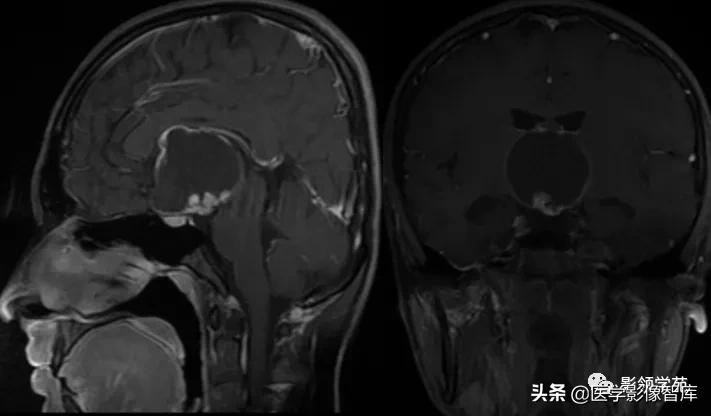

鞍区见一较大肿块,形态不规则,边界清楚,T1WI呈等信号,T2WI呈高低混杂信号;

矢状面和冠状面上可见典型束腰征、雪人征(腺瘤通过鞍膈向上生长时,由于受到鞍膈的限制而形成对称的切迹)。

病灶不均匀 明显强化。视交叉、垂体柄受压上移。

鞍区见一类圆形囊性肿块,呈长T1长T2信号,囊壁厚薄不均。

囊壁呈环状强化,囊内未见明显强化。病灶占据蝶鞍、鞍上池及第三脑室前部,边缘清楚。

鞍区见一类圆形囊性肿块,囊壁呈蛋壳样钙化。肿块向下压入蝶鞍,向上达到第三脑室水平。